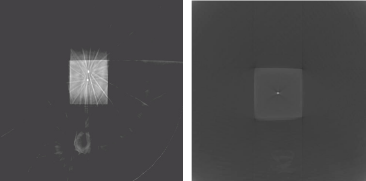

(a) (b)

(c) (d)

사용한 X선의 에너지에 따라 영상의 질이 크게 다르 게 나타나는데, OBI를 이용하여 kilo-voltage 에너지를 사용하는 경우에는 광전효과가 지배적으로 발생하며, EPID mega-voltage의 에너지를 사용한 영상에서는 compton scattering의 발생이 지배적이므로, 방사선과 물질과의 상호작용의 차이가 영상의 질에 영향을 미치고 있다[12,13,14]. 즉 kilo-voltage의 영상에서 선예도와 대 조도가 우수한 back projection 영상을 얻을 수 있었다. Back projection 영상의 상태가 재구성한 CBCT의 영상 에도 영향을 미치며 kilo-voltage 에너지를 사용한 OBI 로부터 얻은 영상으로 재구성한 kV-CBCT가 MV-CBCT에 비하여 선예도와 대조도가 우수함을 보여 주고 있다[Fig. 6].

(e)

images (e) Gated MV-CBCT reconstructed from EPID